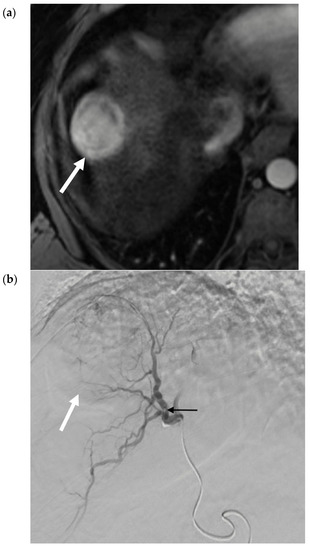

- Riaz, A.; Gates, V.; Atassi, B.; Lewandowski, R.; Mulcahy, M.F.; Ryu, R.K.; Sato, K.T.; Baker, T.; Kulik, L.; Gupta, R.; et al. Radiation Segmentectomy: A Novel Approach to Increase Safety and Efficacy of Radioembolization. Int. J. Radiat. Oncol. 2011, 79, 163–171. [Google Scholar] [CrossRef]

- Padia, S.A.; Kwan, S.W.; Roudsari, B.; Monsky, W.L.; Coveler, A.; Harris, W.P. Superselective Yttrium-90 Radioembolization for Hepatocellular Carcinoma Yields High Response Rates with Minimal Toxicity. J. Vasc. Interv. Radiol. 2014, 25, 1067–1073. [Google Scholar] [CrossRef] [PubMed]

- Lewandowski, R.; Gabr, A.; Abouchaleh, N.; Ali, R.; Al Asadi, A.; Mora, R.; Kulik, L.; Ganger, D.; Desai, K.; Thornburg, B.; et al. Radiation Segmentectomy: Potential Curative Therapy for Early Hepatocellular Carcinoma. Radiology 2018, 287, 1050–1058. [Google Scholar] [CrossRef]